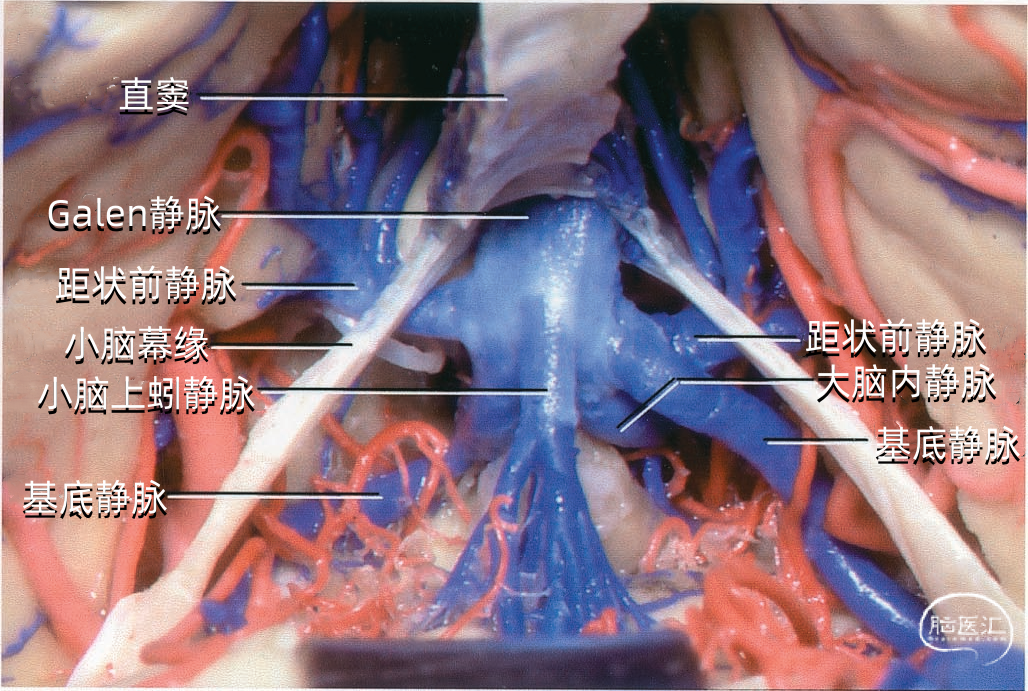

大脑的静脉可分为浅表组和深部组。浅表组引流皮层表面血液;深部组引流深部白质和灰质核团,走行于脑室壁和基底池,最终汇入大脑内静脉、基底静脉和大脑大静脉。本文仅讲解浅表组(大脑浅表静脉)。 由于大脑静脉的大小、吻合存在较多的变异,实际手术操作中有时造成较大的深部静脉主干的闭塞,但却较少引起明显的神经功能缺失,这主要归因于静脉之间存在广泛的吻合。 另一方面,有时这些复杂静脉交通网络的破坏有可能造成严重的功能障碍,如偏瘫、昏迷甚至死亡。有时静脉血管是脑深部肿瘤手术入路的主要阻碍,尤其是松果体区肿瘤,采取经颞下或经上矢状窦中部入路时尤为明显。 因为静脉大多紧贴在脑组织表面走行,而动脉与脑组织贴敷不紧,尤其在脑沟、脑池、裂隙等部位更加松散,因此静脉移位往往比动脉移位更能够提供准确的定位信息。尤其是侧脑室的静脉比动脉更能起到充当解剖标志的作用,当脑室内肿瘤造成脑室壁上各个神经组织结构边界难以辨认,更需要靠静脉血管帮助定位。二、硬膜窦

直窦(straight sinus)位于大脑镰与小脑幕的连接处(下图),起源于胼胝体压部后方,由下矢状窦与大脑大静脉(Galen静脉)汇合而成,汇合处管径膨大,向后于枕内隆凸处注入窦汇。直窦平均长约50mm,呈尖端向上的三角形。此窦多数是下矢状窦的直接延续。大脑大静脉是汇入直窦的最大静脉。直窦向后除注入窦汇外,尚可直接注入横窦,它可以进入任何一侧的横窦,但多数主要汇入左侧的横窦。

从下表面引流入小脑幕窦的静脉包括颞底前静脉,颞底中静脉、颞底后静脉和枕底静脉。 内侧小脑幕窦接受来自小脑的静脉血流,并加入直窦。基底窦位于斜坡。 大脑镰组(上图 紫色)由直接或经由大脑内静脉、基底静脉和大脑大静脉汇入下矢状窦或直窦的静脉构成。汇入直窦的静脉(上图 紫色)或其属支,引流胼胝体附近部分的额叶、顶叶和颞叶内侧部,此组静脉的引流区域大致相当于大脑边缘叶,包括终板旁静脉,额眶后静脉、嗅静脉、胼周前静脉、胼周后静脉,钩回静脉、海马前静脉、颞内侧静脉和距状前静脉。